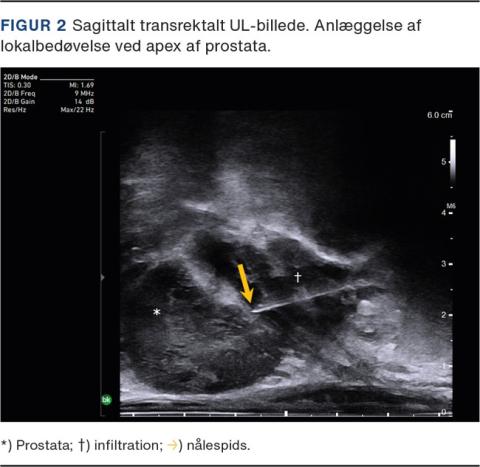

Lokalbedøvelse af prostata

For at blokere innervationen af den prostatiske kapsel injiceres yderligere 5 ml lidocain transperinealt UL-vejledt ved apex af prostata mellem prostatakapslen og levator ani-muskulaturen samt langs den forventede biopsikanal (Figur 2) [13, 14].